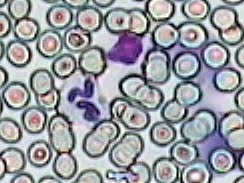

Práctica de Frotis sanguíneo 9